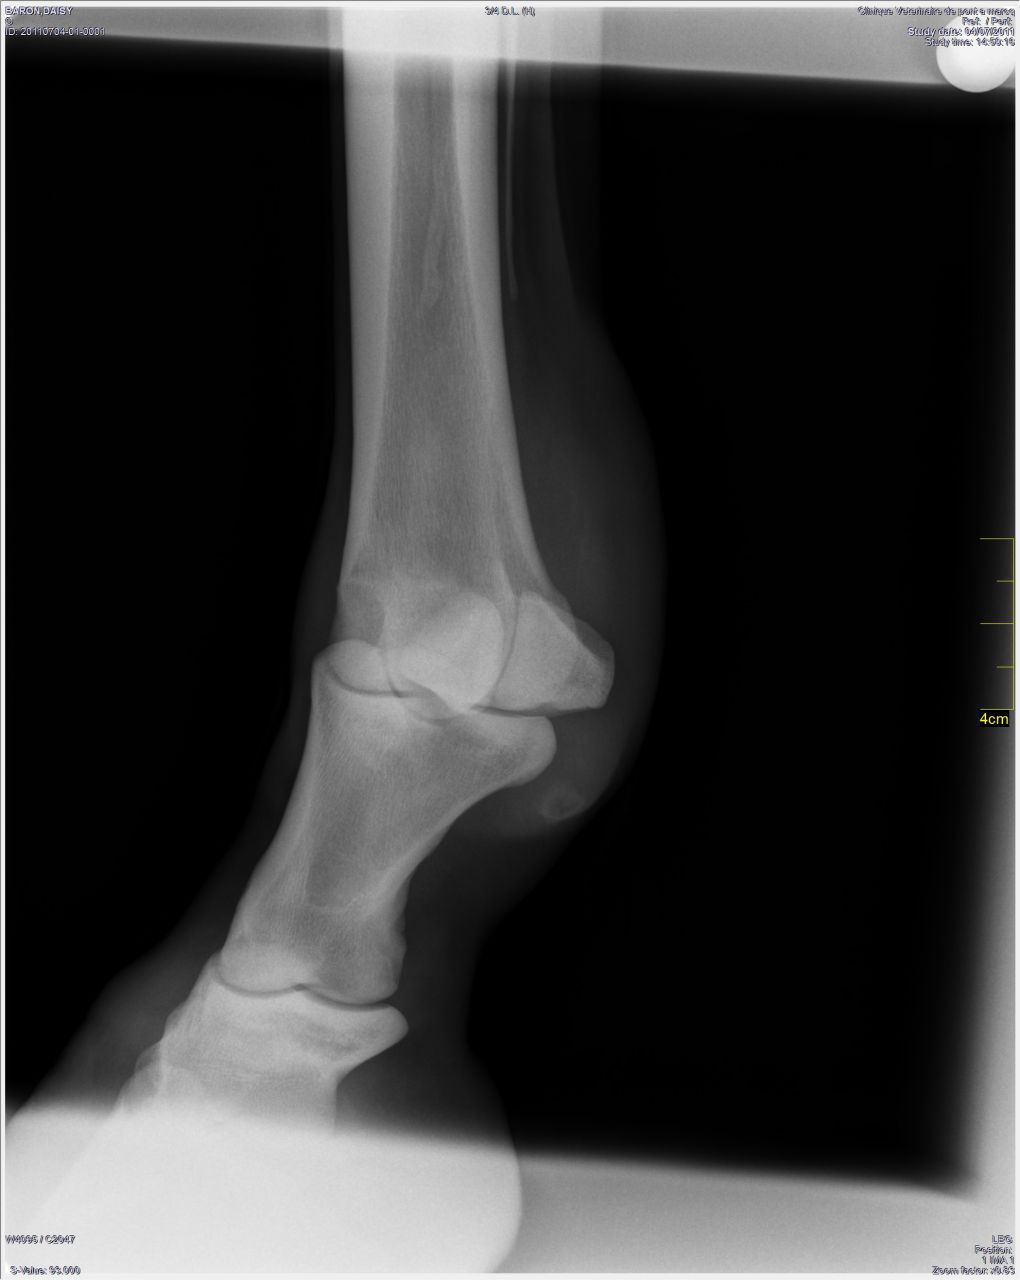

DéconnectéDire merci | Bonsoir, J'ai fait faire une visite d'achat hier . J'ai demandé des radios des antérieurs uniquement . Le vétérinaire n'émet pas d'avis négatif pour l'achat de l'équidé par rapport à l'usage prévu : Loisir / Balade. Cependant , il a détecté une ancienne fourbure et un parage à faire rapidement du fait d'un ferrage relativement ancien . Pouvez vous m'aider à interpréter les radios svp? Selon votre expérience je me lance ou pas ? Merci http://www.netimago.com/images/vf6J8qK3LlDkda0.jpg http://www.netimago.com/images/5plHyMefEFPAz2k.jpg Message édité le 02/09/11 à 18:15 |

| Dire merci | c'est une blague j'espère? on n'interprête pas des radios par forum interposé, et encore moins sur des clichés de qualité moyenne et sans agrandissement possible |

| Dire merci | nan mais c'est juste qu'une interprétation de radio, tu vas pas demander ça sur un forum de cavaliers quand meme, enfin voyons, restons logiques que tu demandes un 2e avis vétérinaire à un confrère du véto qui a fait la VA, ok, mais sur un forum, c'est du grand n'imp et oui, j'ai pu agrandir la radio, mais désolé, pour moi elle est pas d'assez bonne qualité pour pouvoir tout voir, voila "mon" interprétation |

| Dire merci | Le problème, c'est que ceux qui disent "ça ne m'arrête pas" sont probablement capables (enfin, j'espère) de gérer un cheval fourbu. Je connais un poney que j'aime beaucoup, qui en est à sa 3ième fourbure... Je sais pourquoi et ça ne me ferait pas peur "d'hériter" de ce poney. Par contre, pour un premier cheval, avec peu d'expérience, je ne crois pas que je prendrais. Sur les radios, le cheval est ferré en plus... Ce qui n'est pas la meilleure chose pour un fourbu. Bref, tu voulais des avis, tu en as dans tous les sens. Et je le répète, je comprends parfaitement, pourquoi, en pro, al a répondu si impulsivement. |